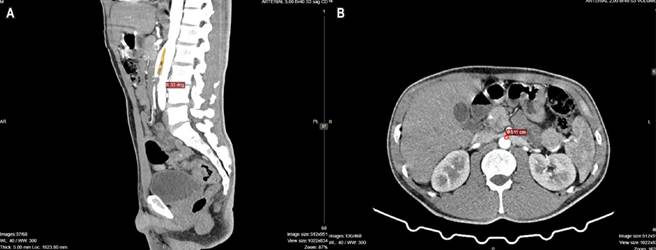

En previas hospitalizaciones se documentó el manejo sintomático del dolor con mejoría parcial. Por parte del servicio de Medicina Interna y ante la persistencia del dolor, se solicitó una tomografía axial computarizada (TAC) de doble contraste que reportó una dilatación entre la segunda y tercera porciones del duodeno, y se observó una zona de transición a nivel de la pinza aortomesentérica, con una disminución del ángulo entre la arteria mesentérica superior y la aorta menor de 8º, con una amplitud del espacio aortomesentérico de 5 mm, sin dilatación o estenosis de la vena renal izquierda, lo que condiciona un síndrome por compresión aortomesentérico-duodenal (Figura 1).

Imágenes propiedad de los autores.

Figura 1 Tomografía de abdomen total doble contraste. A. Corte sagital, fase arterial. Se visualiza la pinza aortomesentérica con un ángulo de 8º. B. Corte transversa, fase arterial. Se visualiza la distancia aortomesentérica de 5 mm.

El paciente de este caso presentó una angulación de 8º y una distancia de 5 mm. Aunque no existe una subclasificación dependiente del grado de estrechamiento o su distancia del ángulo, consideramos estos valores significativos para generar la sintomatología descrita en el caso. El síndrome de Wilkie puede ser congénito o adquirido, y dentro de los factores de riesgo del síndrome adquirido se encuentra la pérdida de peso secundaria a malignidad, cirugía bariátrica, trastornos de la conducta alimenticia, insuficiencia cardíaca, cirugías de columna que ocasionen tracción vertical, traumatismos, quemaduras, hospitalizaciones prolongadas, desnutrición, procesos infecciosos crónicos o síndromes de malabsorción que ocasionen una rápida pérdida de la grasa intraabdominal del mesenterio y la consecuente disminución del diámetro y ángulo de la pinza3,6,8. Este paciente no presentó ningún factor de riesgo relacionado, como en el 40% de los casos descritos en la literatura11; sin embargo, se considera que la pérdida de peso en los últimos meses pudo ser no solo consecuencia de su estrechamiento sino contribuir más a la gravedad de los síntomas dada la pérdida de la grasa mesentérica8.